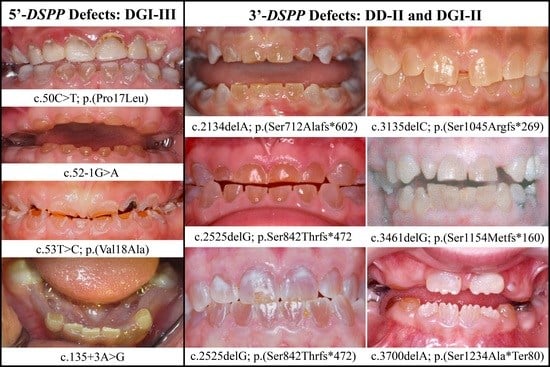

3.2. Four Families with DGI-III: 5′ DSPP Mutations

| 5 | Exon 2 | g.7430C>T | c.50C>T | p.(Pro17Leu) | Family 1, [61,62,63] |

| 15 | Exon 3 | g.8578T>C | c.53T>C | p.(Val18Ala) | Family 3 |

| 21 | Intron 3 | g.8663A>G | c.135+3A>G | p.(?) | Family 4 [78] |

| 1 | Illumina HiSeq 2500 (WES) | NG_011595.1:g.7430C>T; NM_014208.3:c.50C>T; NP_055023.2:p.(Pro17Leu) | Missense | II:6, unaffected mother: 136.75× III:5, affected 1st child: 159.3× III:6, affected 2nd child: 129.86× |

| 2 | Illumina HiSeq 2500 (WES) | NG_011595.1:g.8576G>A; NM_014208.3:c.52-1G>A | Splice Acceptor | IV:2, affected 2nd child: 177.72× |

| 3 | Illumina HiSeq 2500 (WES) | NG_011595.1:g.8578T>C; NM_014208.3:c.53T>C; NP_055023.2:p.(Val18Ala) | Missense | III:2, affected mother: 285.78× IV:2, affected child: 189.42× |

| 4 | Sanger Sequencing | NG_011595.1:g.8663A>G; NM_014208.3:c.135+3A>G | Splice Donor | |